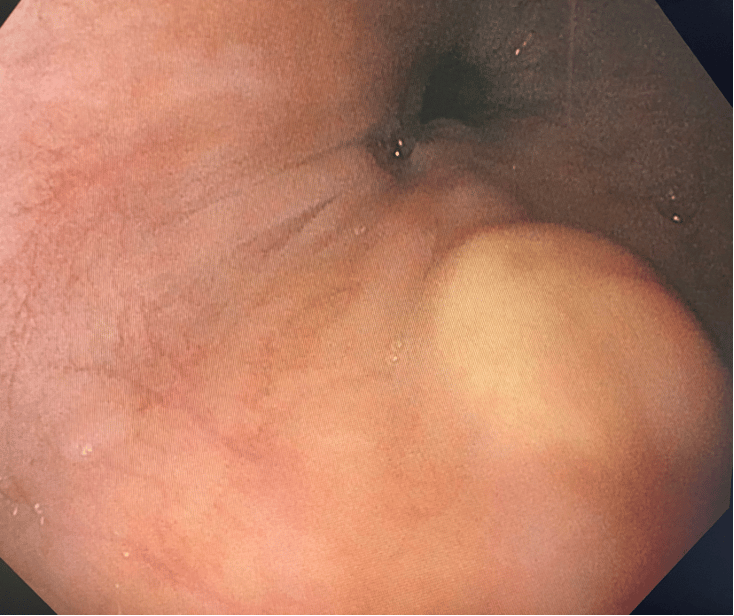

Granular Cell Tumor (GCT)

Although some guidelines dichotomize the decision to resect granular cell tumors (also called Abrikosoff's tumor) based on presence or absence of symptoms, others, including ourselves support the decision to resect based in histological criteria.

Let's not forget that GCT can be malignant from the outset, regardless of their size or presence of symptoms. Indeed, GCT are classified as malignant, benign and indeterminate. Furthermore, 2% of benign GCT progress to malignancy.

Thus, I like to use the classification of Fanburg-Smith (see table), which takes various histological features into consideration, such as tumor necrosis, spindle cells, vesicular nuclei with prominent nucleoli, mitotic activity (>2 mitosis/10 high-power fields), high nucleocytoplasmic ration, nuclear pleomorphism.